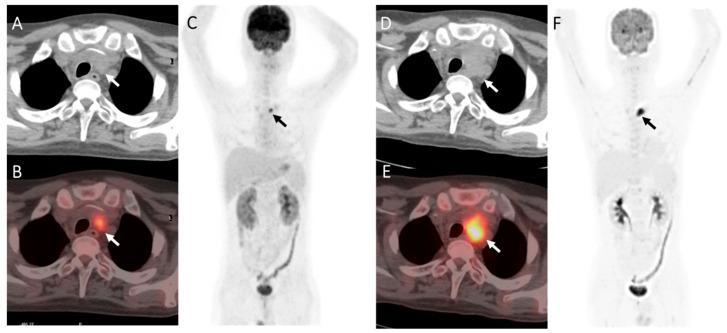

A total of 185 patients (235 post-transplantation PET/CT scans) were enrolled in our present study. Compared with those with true-positive PET results, patients with false-positive PET results exhibited a better prognosis. For the autologous SCT group, false-positive cases were more commonly seen when FDG-avid foci appeared outside the sites of the original disease ( = 0.004), and the integrated CT imaging showed negative results ( = 0.000). In multivariate logistic regression analysis, integrated CT results were the only significant factor. For the allogeneic SCT group, false-positive cases were significantly more commonly seen when DS = 4 ( = 0.046), FDG-avid foci appeared outside the sites of the original disease ( = 0.022), and the integrated CT imaging showed negative results ( = 0.001). In a multivariate logistic regression analysis, whether FDG-avid foci were in the sites of the original disease and integrated CT results were both significant factors.

False-positive FDG uptake in post-transplantation PET was not uncommon. Several variables could provide an important reference to differentiate false-positive from true-positive post-SCT PET results for lymphoma involvement.